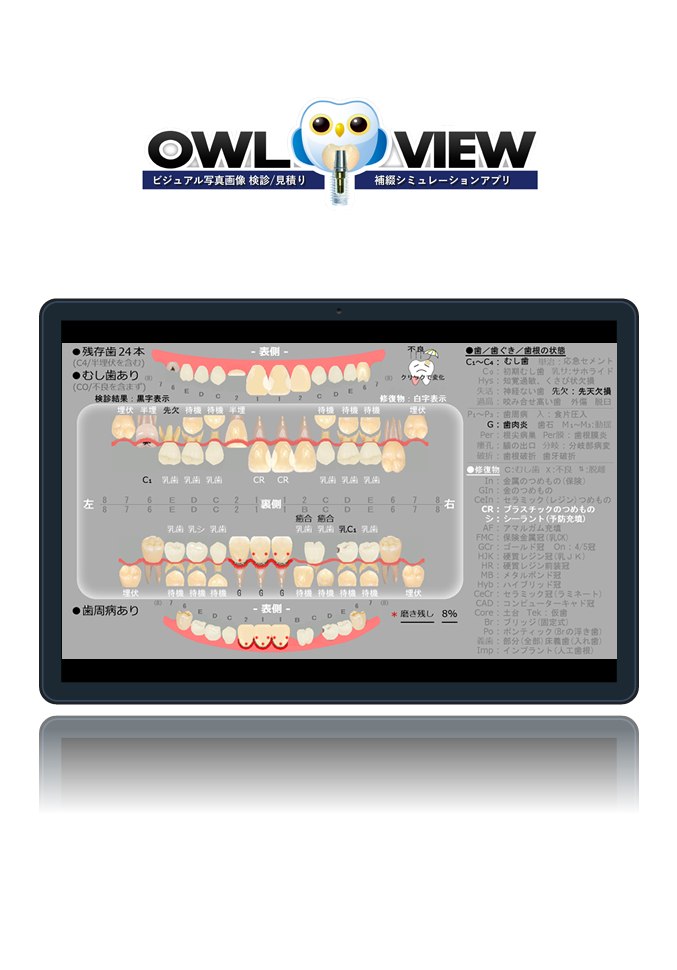

ビジュアルな写真画像での歯管、検診書類を正確、簡単、1シートで!

今まで何枚もの検診情報がたった1枚で。

歯科医師と患者様の為に開発されました

より便利に、より分かりやすく。

検診/歯管

これはサンプルの説明文です。各箇所に短めの説明文を入れます。これはサンプルの説明文です。各箇所に短めの説明文を入れます。